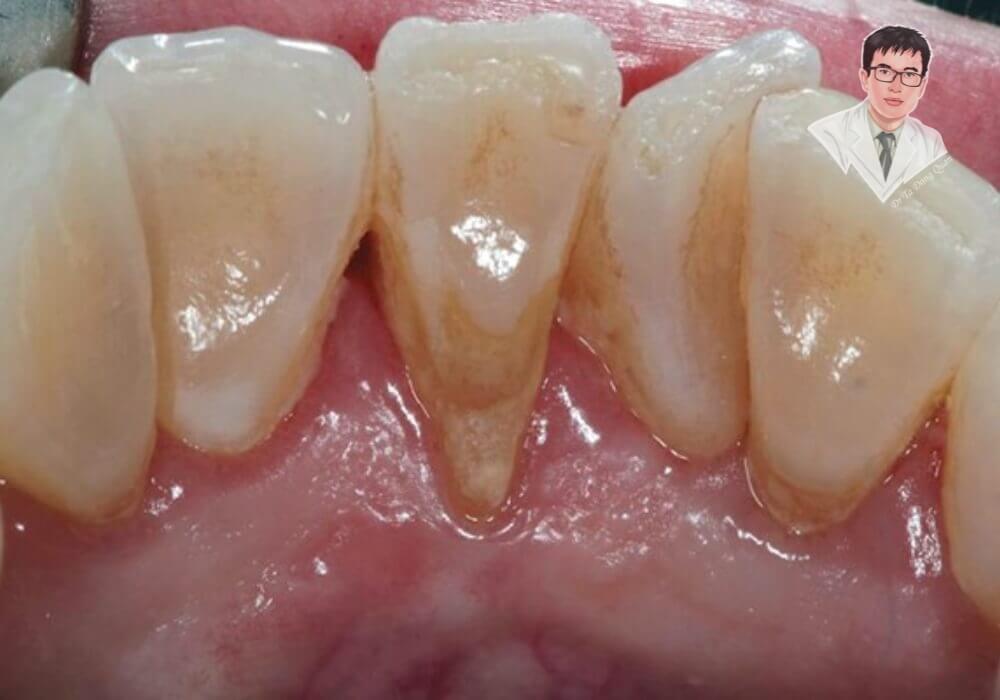

Tụt nướu chân răng là tình trạng mô lợi bao quanh răng dần co lại, khiến chân răng lộ ra ngoài. Điều này làm mất đi sự bảo vệ tự nhiên, dễ gây ê buốt và tạo điều kiện cho vi khuẩn tấn công gây các bệnh lý nha chu. Hình ảnh trước và sau khi tụt lợi sẽ giúp bạn dễ dàng nhận biết rõ hơn vấn đề này, từ đó chủ động bảo vệ sức khỏe răng miệng.

Khi tình trạng tụt nướu chân răng tiến triển, các dấu hiệu sẽ trở nên rõ ràng hơn. Chân răng bị lộ ra ngoài rõ rệt, nướu tụt sâu tạo thành khe hở giữa các răng, dễ mắc thức ăn gây khó chịu và mất thẩm mỹ. Ở giai đoạn muộn, răng có thể lung lay, báo hiệu nguy cơ mất răng nếu không được điều trị kịp thời.